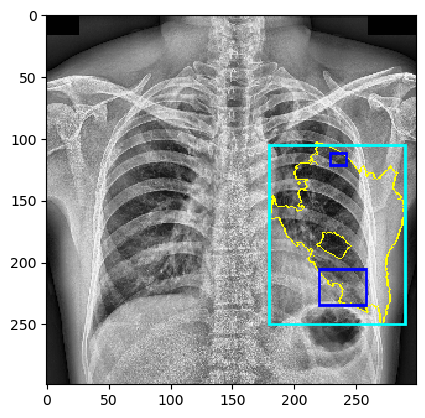

The VinDr-CXR dataset includes 15,000 images within its training set, with labels manually defined by a team of radiologists. Figure 3 presents sample images from this dataset. The dataset includes 22 local labels represented by bounding boxes surrounding abnormalities, and six global labels denoting detected diseases. The images are provided in the Digital Imaging and Communications in Medicine (DICOM) format, accompanied by relevant DICOM tags such as patient sex and age. Primarily consisting of posterior-anterior (PA)-view chest X-rays, the dataset excludes non-relative X-rays from other body parts [23].